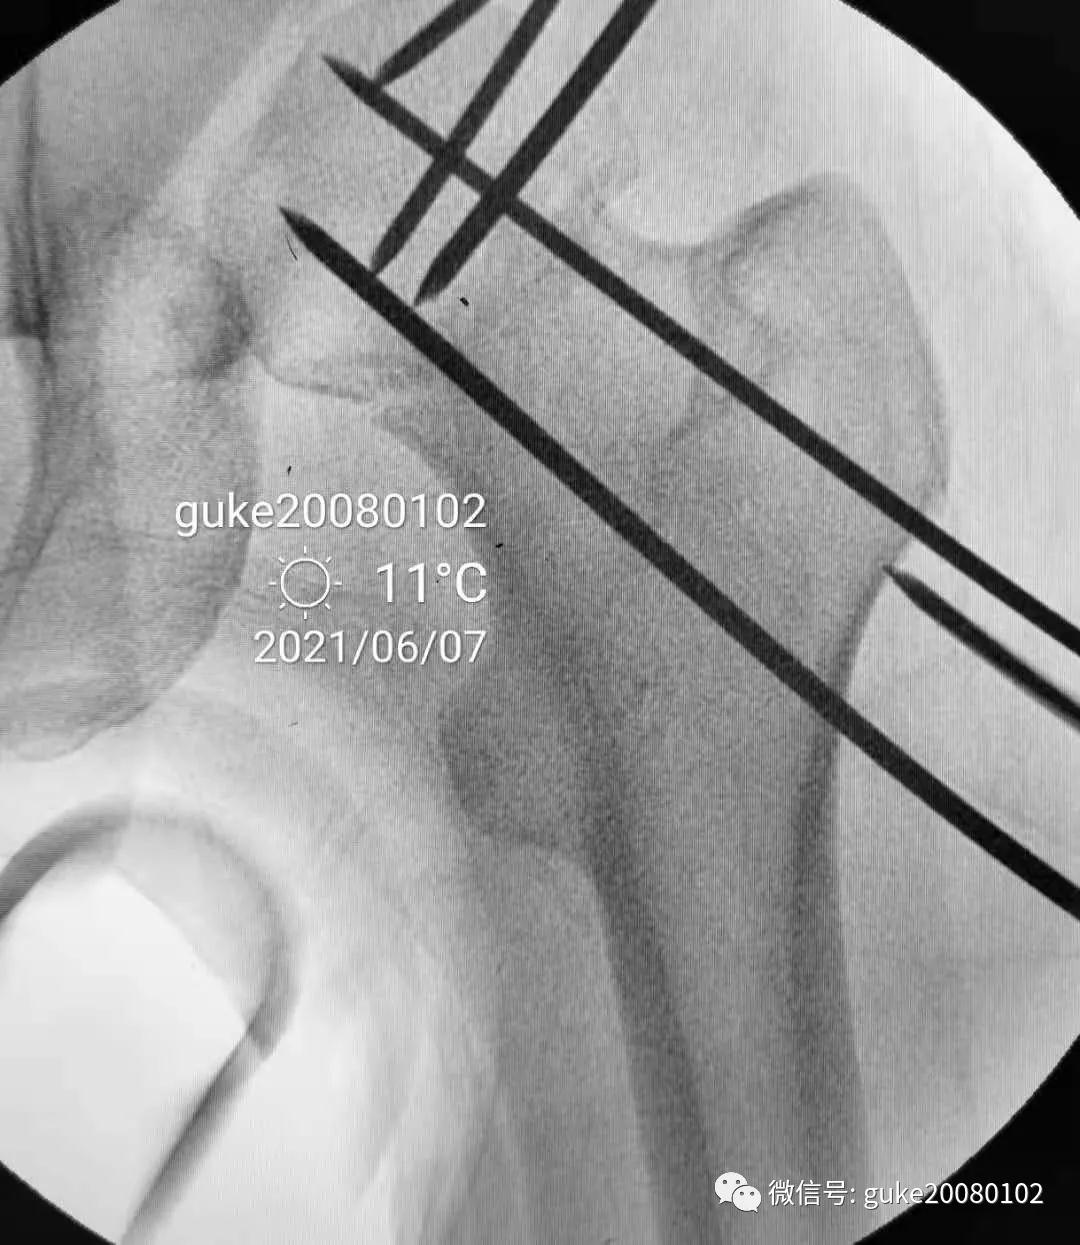

患者置于牵引床上,固定骨盆,尝试Ledbetter法复位,透视见复位不佳。骨折断端崁插,股骨头外翻。

- 在大转子顶点近端5厘米处,经皮向股骨头上方插入直径2.0mm克氏针两枚,敲击克氏针至骨质,撬拨头颈骨折块复位。

- 撬拨力量偏小,骨折复位不足。再插入一枚2.5mm克氏针,接力撬拨,骨折复位。

1.正侧位观察骨折复位,骨小梁走形恢复。崁插骨折复位。